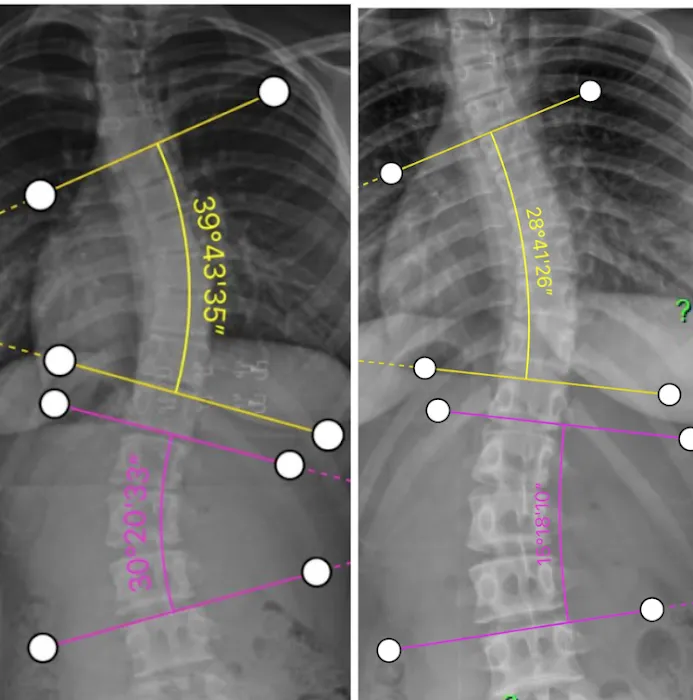

The philosophy at the Scoliosis Correction Center is built on a deep understanding of spinal biomechanics and a commitment to non-surgical intervention. Scoliosis, a condition characterized by a lateral curvature of the spine, can cause a range of issues, from back pain and postural imbalances to reduced mobility. The center’s approach is to provide a conservative, gentle, and effective alternative to surgery. They utilize a variety of specialized chiropractic techniques and rehabilitative exercises designed to correct spinal curvature, strengthen supporting muscles, and improve overall spinal health. This focused expertise is a significant advantage, as it allows the team to develop highly personalized and targeted treatment plans for each patient's unique curve and condition.

- Scoliosis Correction Programs: The primary service of the clinic, these programs are designed to reduce the curvature of the spine, improve posture, and alleviate associated pain without the need for invasive surgery.

- Non-Surgical Spinal Care: The center provides a conservative and gentle approach to spinal health, utilizing specialized chiropractic adjustments and techniques tailored to the unique needs of scoliosis patients.

- Personalized Treatment: The team understands that no two spines are alike. They create individualized treatment plans based on a thorough examination and a detailed understanding of a patient's specific spinal curve.